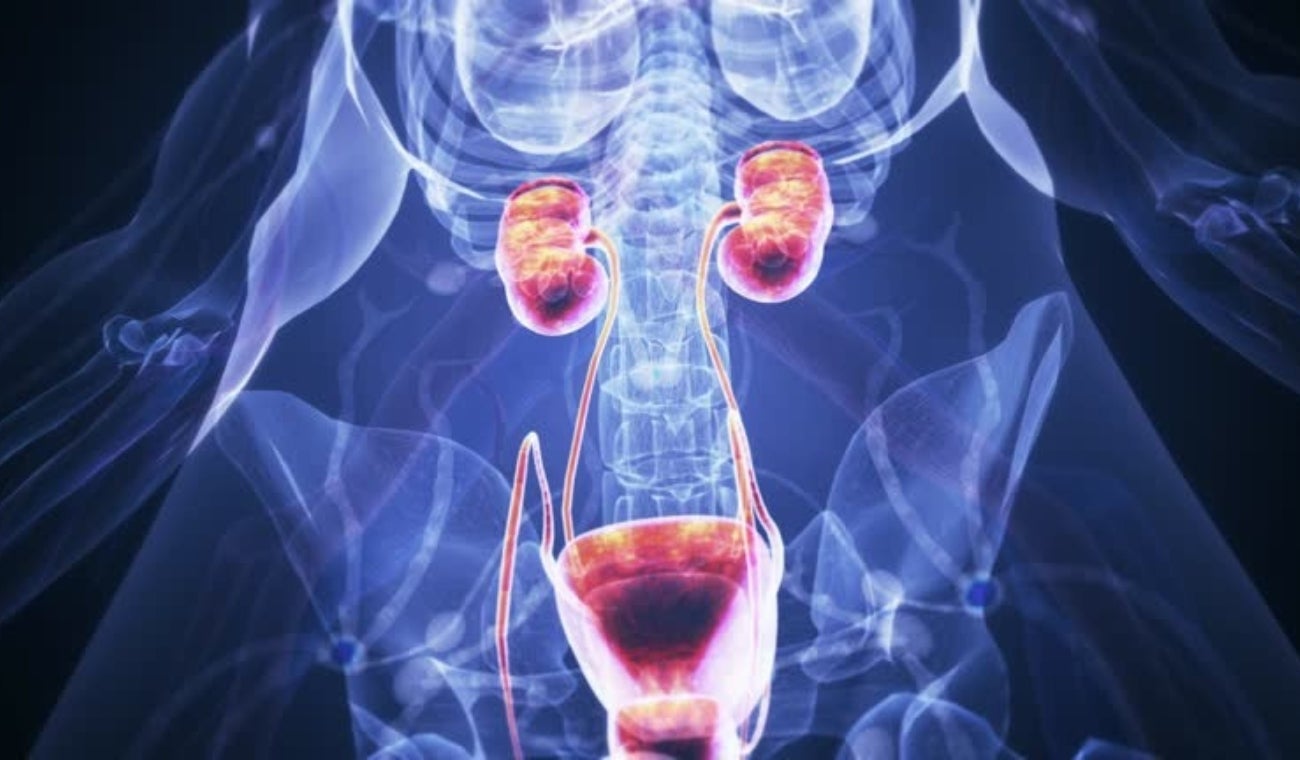

Últimas noticias sobre Riñón

“Me demoré cuatro años consiguiendo un trasplante de riñón, estoy en riesgo de perderlo por falta de medicamentos": paciente trasplantado

La falta de entrega de medicamentos pone en riesgo el trasplante de riñón por el que esperó cuatro años.

Riñón

Causas comunes de la enfermedad renal crónica en gatos y cómo prevenirla, según un experto veterinario